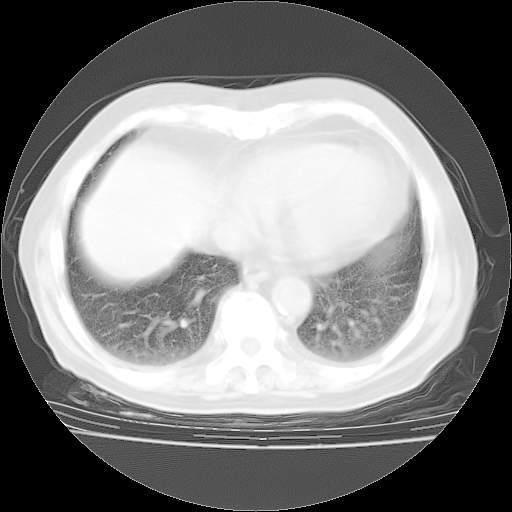

4月28日肺部CT——再次出现类似去年5月9日——透光度降低,“间质性”改变。

个人阅读4.14日肺部CT平扫:纵隔窗无异常,但肺窗示:双下肺内、后基底段有片絮状侵润影,部位以后基底段为著,以间质改变为主,呈急性肺泡炎征像,和首次住院影像学有相似之处。仅是个人读片,明日请相关专家再读片哈。其它建议同上。

1、108#的是4月14日的胸部CT(发此贴时还没看着28日的CT)。14日的胸部CT其实已经出现改变(如108#所述),个人认为28日的胸部CT除纵膈窗疑似有双侧胸膜增厚或少量胸积液(可行胸部B超明确)外,与4月14日对照病变有所加重;2、已经给予“异烟肼、利福平、乙胺丁醇”抗痨治疗?如果是,甲强龙80mg可缓慢减量;如果环磷酰胺已停用,暂不使用;3、中性粒细胞92%,明显升高,目前体温情况?注意合并细菌感染可能,使用左氧氟沙星情况下,是否联用B-内酰胺类抗菌药物?另外是查免疫全套非风湿全套。